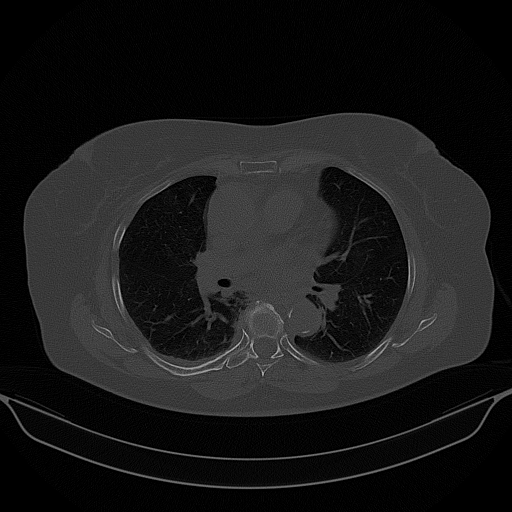

Generated VENOUS CT scan (A→B translation)

No window - Raw intensity values

Lung window (WL -600, WW 1500 β†’ Low βˆ’1350, High +150)

Mediastinum window (WL 40, WW 400 β†’ Low βˆ’160, High +240)